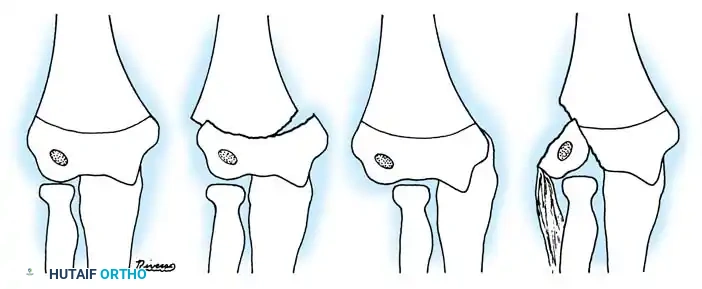

Fig. 33-38 Wilkins classification of radial neck fractures. A, Salter-Harris type II fracture. B, Salter-Harris type IV fracture. C, Salter-Harris type I fracture.

The Wilkins Classification System:

* Type A: Salter-Harris type I and II injuries of the proximal radial epiphyses.

* Type B: Salter-Harris type IV injuries of the proximal radial epiphyses.

* Type C: Fractures involving exclusively the proximal radial metaphysis.

* Type D: Fractures occurring iatrogenically when a dislocated elbow is being reduced.

* Type E: Fractures occurring simultaneously in conjunction with an elbow dislocation.

Fig. 33-39 A, Fracture occurring when elbow dislocation is reduced. B, Fractures occurring at time of elbow dislocation.

Fractures can present as angulated, translocated (shifted), or totally displaced. In the context of an elbow dislocation, the proximal fragment may become loose within the joint space or trapped, acting as a mechanical block to reduction.

Fig. 33-40 Examples of angulation, translocation, and total displacement of radial neck fractures.